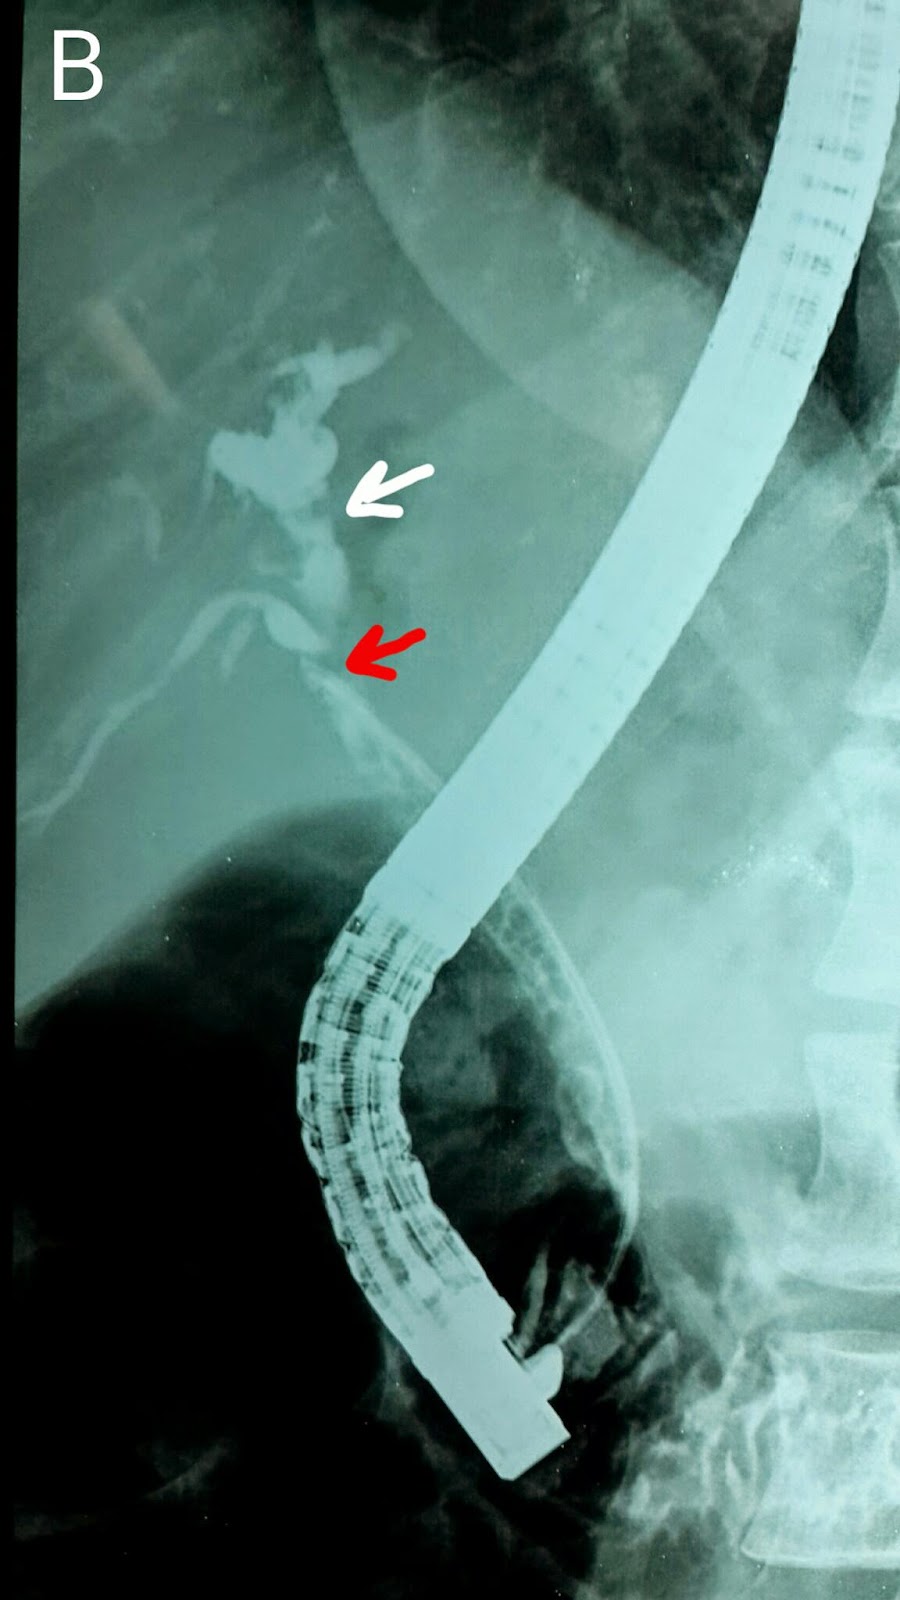

This was this 24 year old's fifth follow up visit. We removed the stent placed in his last visit http://ercp365.blogspot.com/2014/09/fourth-follow-up-ercp-for-post.html. Contrast injection showed a persistent stricture (A: Black arrows). We used a 10mm stricture dilatation balloon of 3cm length to dilate the stricture (B & C: Black arrows show the inflated balloon and red arrow marks the "waist"of the balloon at the strictured segment in B). Marked improvement in the previously narrowed site of ductal anastomosis was noted (D: Black arrows).